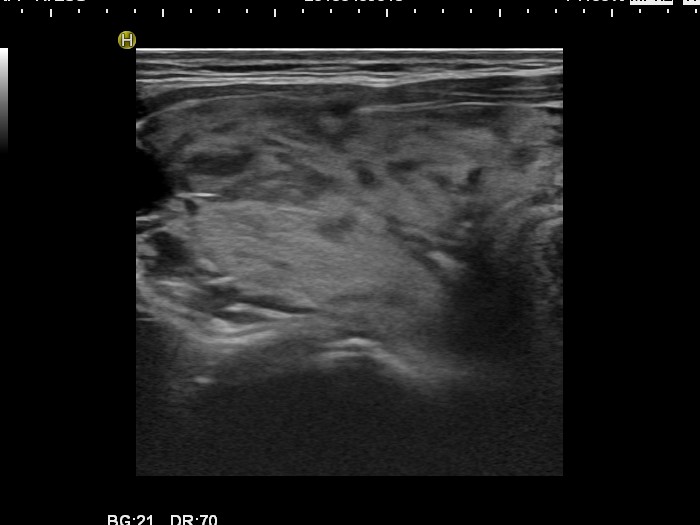

Follow-up investigation 30 months after first visit (ultrasonographic picture 1)

Patient one year after discontinuation of thyrostatics in hyperthyroid state

Right lobe, transverse scan. The echogenicity index is around 20%.